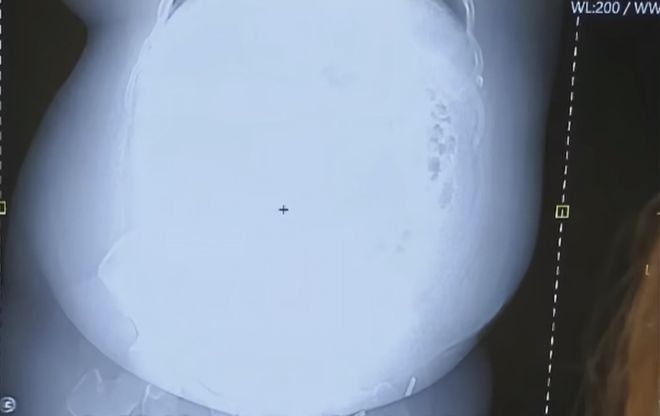

放射线在大胃袋面前也略显乏力,无法穿透脂肪下面的内脏,X光片显示的结果是一团白雾,再资深的医生看了良子的X光片都要冒几滴冷汗,网友建议“不如直接换成伽马射线吧”。